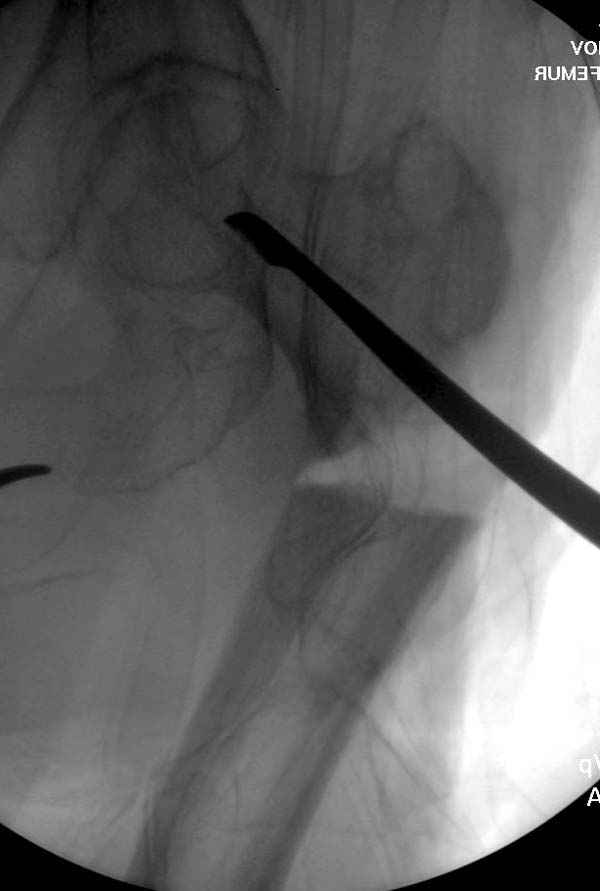

[Ortho] Ятрогенный подвертельный перелом

Не стали усложнять интрамедуллярным вариантом коррекции, легче контролировать коррекцию пластиной, поэтому сделали операцию 95 градусной Blade Plate, разогнув до 110 градусов.

Надеемся на успех, потому что до введения пластины дефект от импланта забили костной стружкой и удалось создать компрессию между отломками, максимальную для импланта (150 кило/паунд). Сделана дополнительная костная пластика и за счет измененного угла пластины устранено укорочение конечности.

Страйкер предоставил отличный инструмент - крючок для удаления длинного гвоздя. Считаем, что врачебная ошибка по установке привела к несостоятельности импланта и к ятрогенному осложнению.